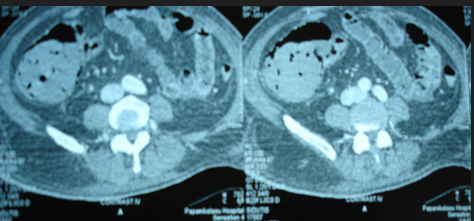

Mesenteric root infiltration — Absolute contraindication for cytoreductive surgery (Courtesy Dr. V. Penopoulos)